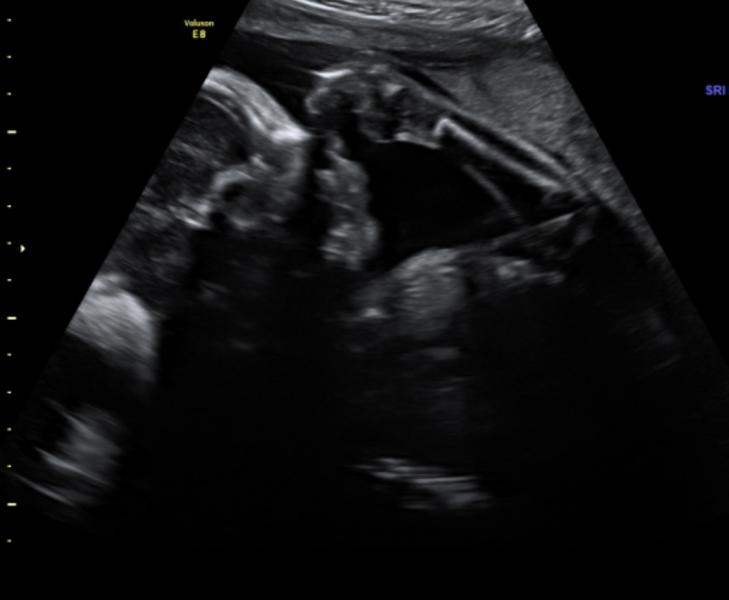

Вес 2200 срок 34,5 , оба в головном . Кровоток в норме , все органы у мальчиков в норме . Сердечко работает как надо .. даже мозг детально изучали . Короче Ура!!

Да какой там 🥲 там такое месиво было - это вообще 🤣🤣🤣